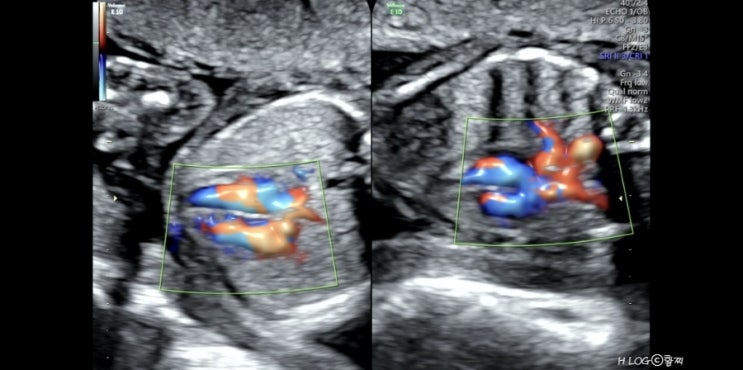

[임신 24, 25주] 임당검사, 입체초음파

내가 벌써 7갤이라니.. 시간 너무 빠르다? 출산하기전에 빨리 놀아야되는데 잘 놀기보다 잘 먹는중 ㅋㅋ...